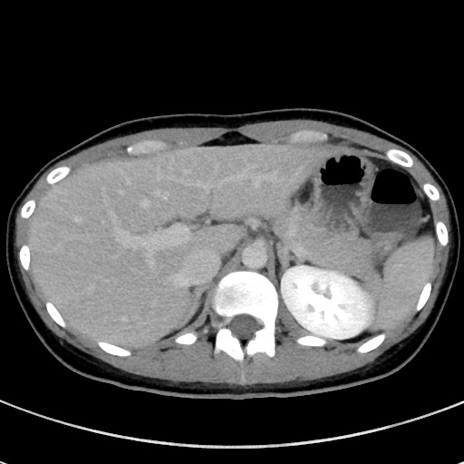

症例17(横断像)

【症例】20歳代女性

【主訴】嘔吐、下腹部痛

【現病歴】昨日夕食後に嘔吐し下腹部痛が出現。本日になっても嘔吐持続し改善しないため来院。

【身体所見】意識清明、BT 37.2℃、BP 108/67mmHg、腹部:平坦、やや硬、下腹部正中から右にかけて圧痛あり、反跳痛軽度あり、tapping pain(+)。

【データ】WBC 13600、CRP 14.94